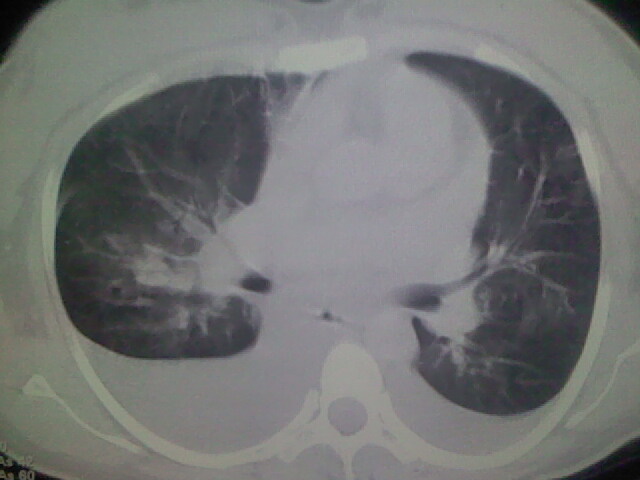

女,24,剖腹产后,突觉胸痛,干咳,不能平卧

考虑肺梗塞、肺水肿,双侧胸腔积液

全心衰导致积液、肺水肿。不知手术前有无心脏病变?

产后心衰